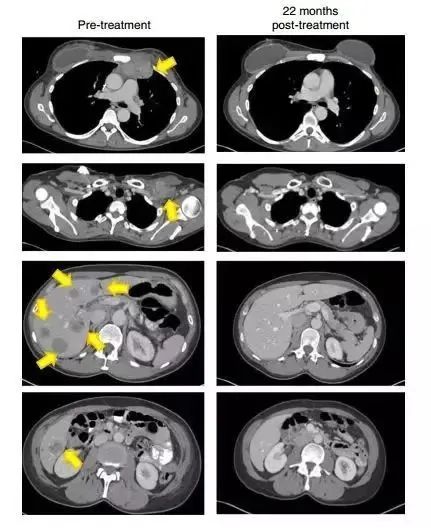

2018年,全球首位接受新型免疫疗法TIL(肿瘤浸润淋巴细胞疗法)的晚期乳腺癌患者Judy Perkins的成功案例就引起了广泛关注。

她在经历了癌症复发、多种治疗无效后,参与了新型免疫疗法TIL疗法试验,最终体内的肿瘤被完全清除,该经典案例也登上了顶级期刊《Nature》上。